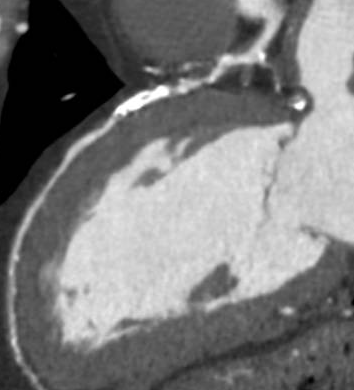

Coronary angiography showed multivessel coronary artery disease, including a severe, long stenosis in a large posterolateral branch of the right coronary artery (RCA), diffuse severe disease in the left circumflex artery (LCX), and a severely calcified chronic total occlusion (CTO) of the mid left anterior descending artery (LAD).

Antegrade wire escalation was attempted using a Corsair ProXS 135 cm (Asahi Intecc) and multiple guidewires, including the Fielder XT, Gaia Next 2, and Gaia Next 3 (Asahi Intecc). However, none of the guidewires were able to successfully cross the occlusion. Hydrodynamic recanalization (HDR) was then attempted. Followig a 0.5 cc tip injection of contrast no progress was achieved. A second HDR injection was performed, after which a Gaia Next 2 guidewire successfully crossed the CTO to the distal LAD. However, the Corsair Pro XS microcatheter failed to cross the distal cap and became fatigued during manipulation. An anchoring technique with a 1.5 ¡¿ 15 mm SC balloon in the septal branch was performed in an attempt to support crossing of the Caravel microcatheter (Asahi Intecc), but the distal cap remained uncrossoable. Caravel microcatheter was left within the CTO body, and a floppy Rotawire Drive guidewire (Boston Scientific) was advanced to the distal LAD. Rotational atherectomy was then carried out with a 1.5 mm burr using the Rotapro system (Boston Scientific) at 180,000–200,000 rpm for a total of 8 minutes. IVUS imaging using Opticross (Boston) confirmed true lumen crossing, presence of circumferential calcification, reverberation as well as superficial plaque fractures. Sequential predilatation with a Wolverine cutting ballon was performed and then definite stenting was accomplished with a 3.5x48 mm and 4.0x38 mm Synergy XD extending from mid LAD into left main